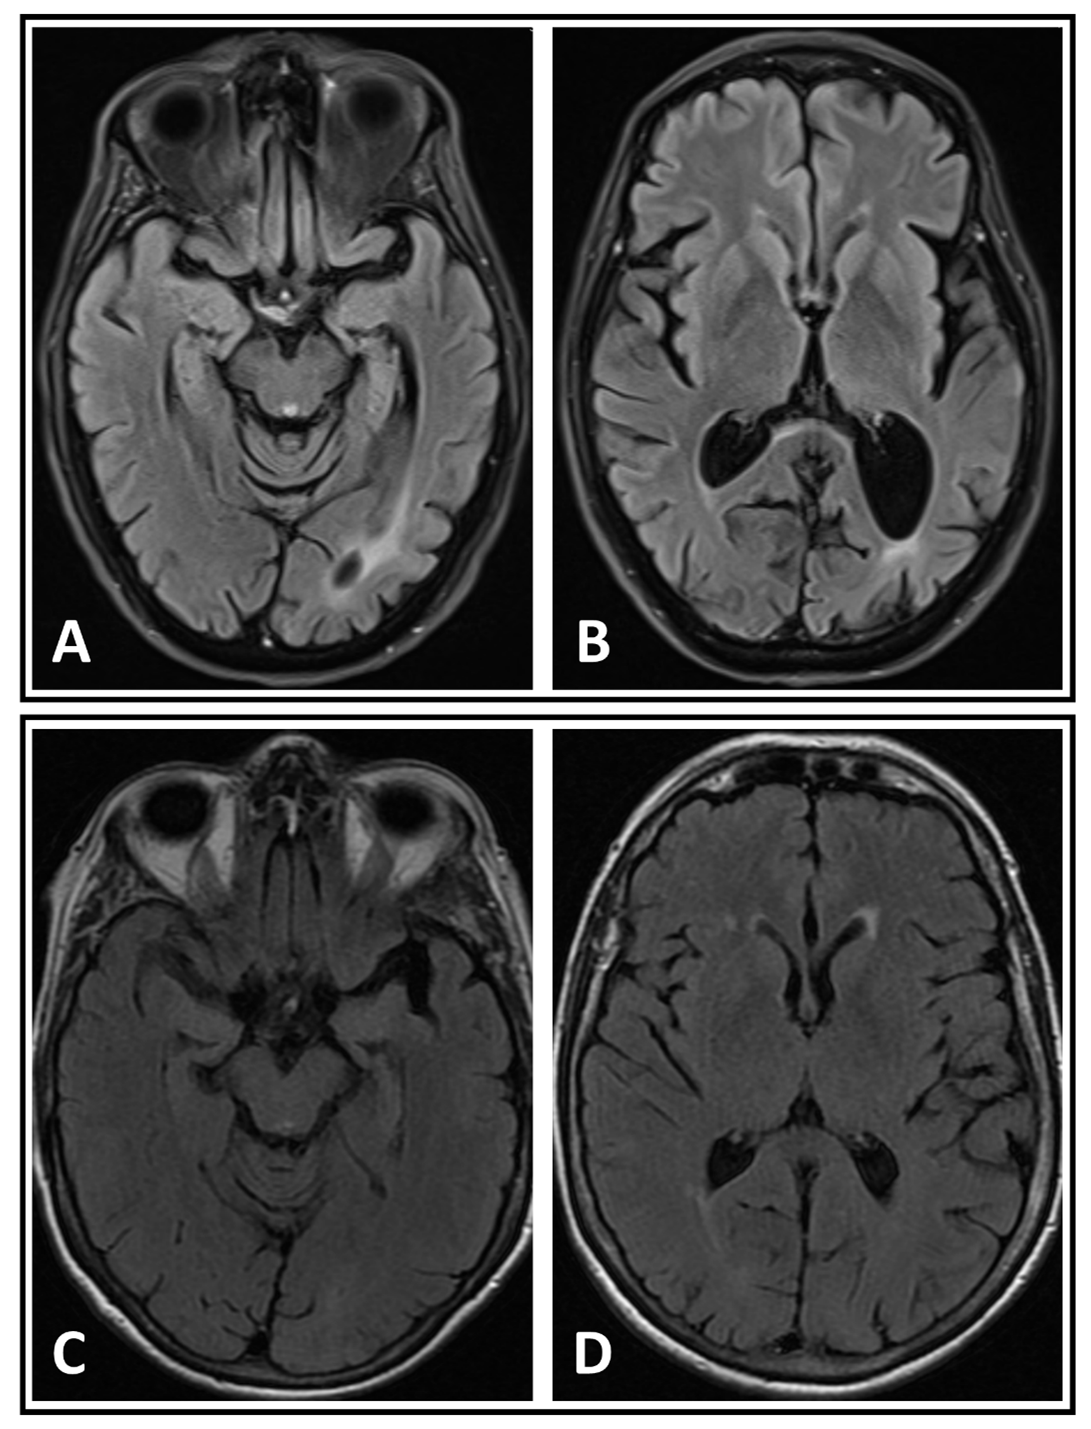

Method: Two patients with atypical parkinsonism were evaluated in the neuro-ophthalmology clinic after being found to have persistent homonymous hemianopsia on both confrontation visual field exam and formal automated perimetry visual field testing. Further diagnostic tests were performed to investigate the potential etiology of their atypical parkinsonism and visual field deficits.

Results: Both patients also exhibited features of simultanagnosia and color agnosia on formal neuro-ophthalmological testing. They also had evidence of cognitive impairments as evident by low Montreal Cognitive Assessment (MoCA) scores. Neuro-imaging did not reveal corresponding cerebral lesion, specifically in the occipital lobes. One patient was later diagnosed with corticobasal syndrome, while the other patient had Dementia with Lewy Bodies.

Conclusion: We propose that the visual field defects in our patients were likely due to the co-existing posterior cortical atrophy (a variant of Alzheimer’s disease) in addition to their atypical parkinsonism. These two cases highlight the potential implications of the comorbid neurodegenerative diseases. Clinicians should conduct extensive counselling with patients and their care partners to adapt to the progressive visual deficits and other neurological deficits the patients may experience as their diseases progress.